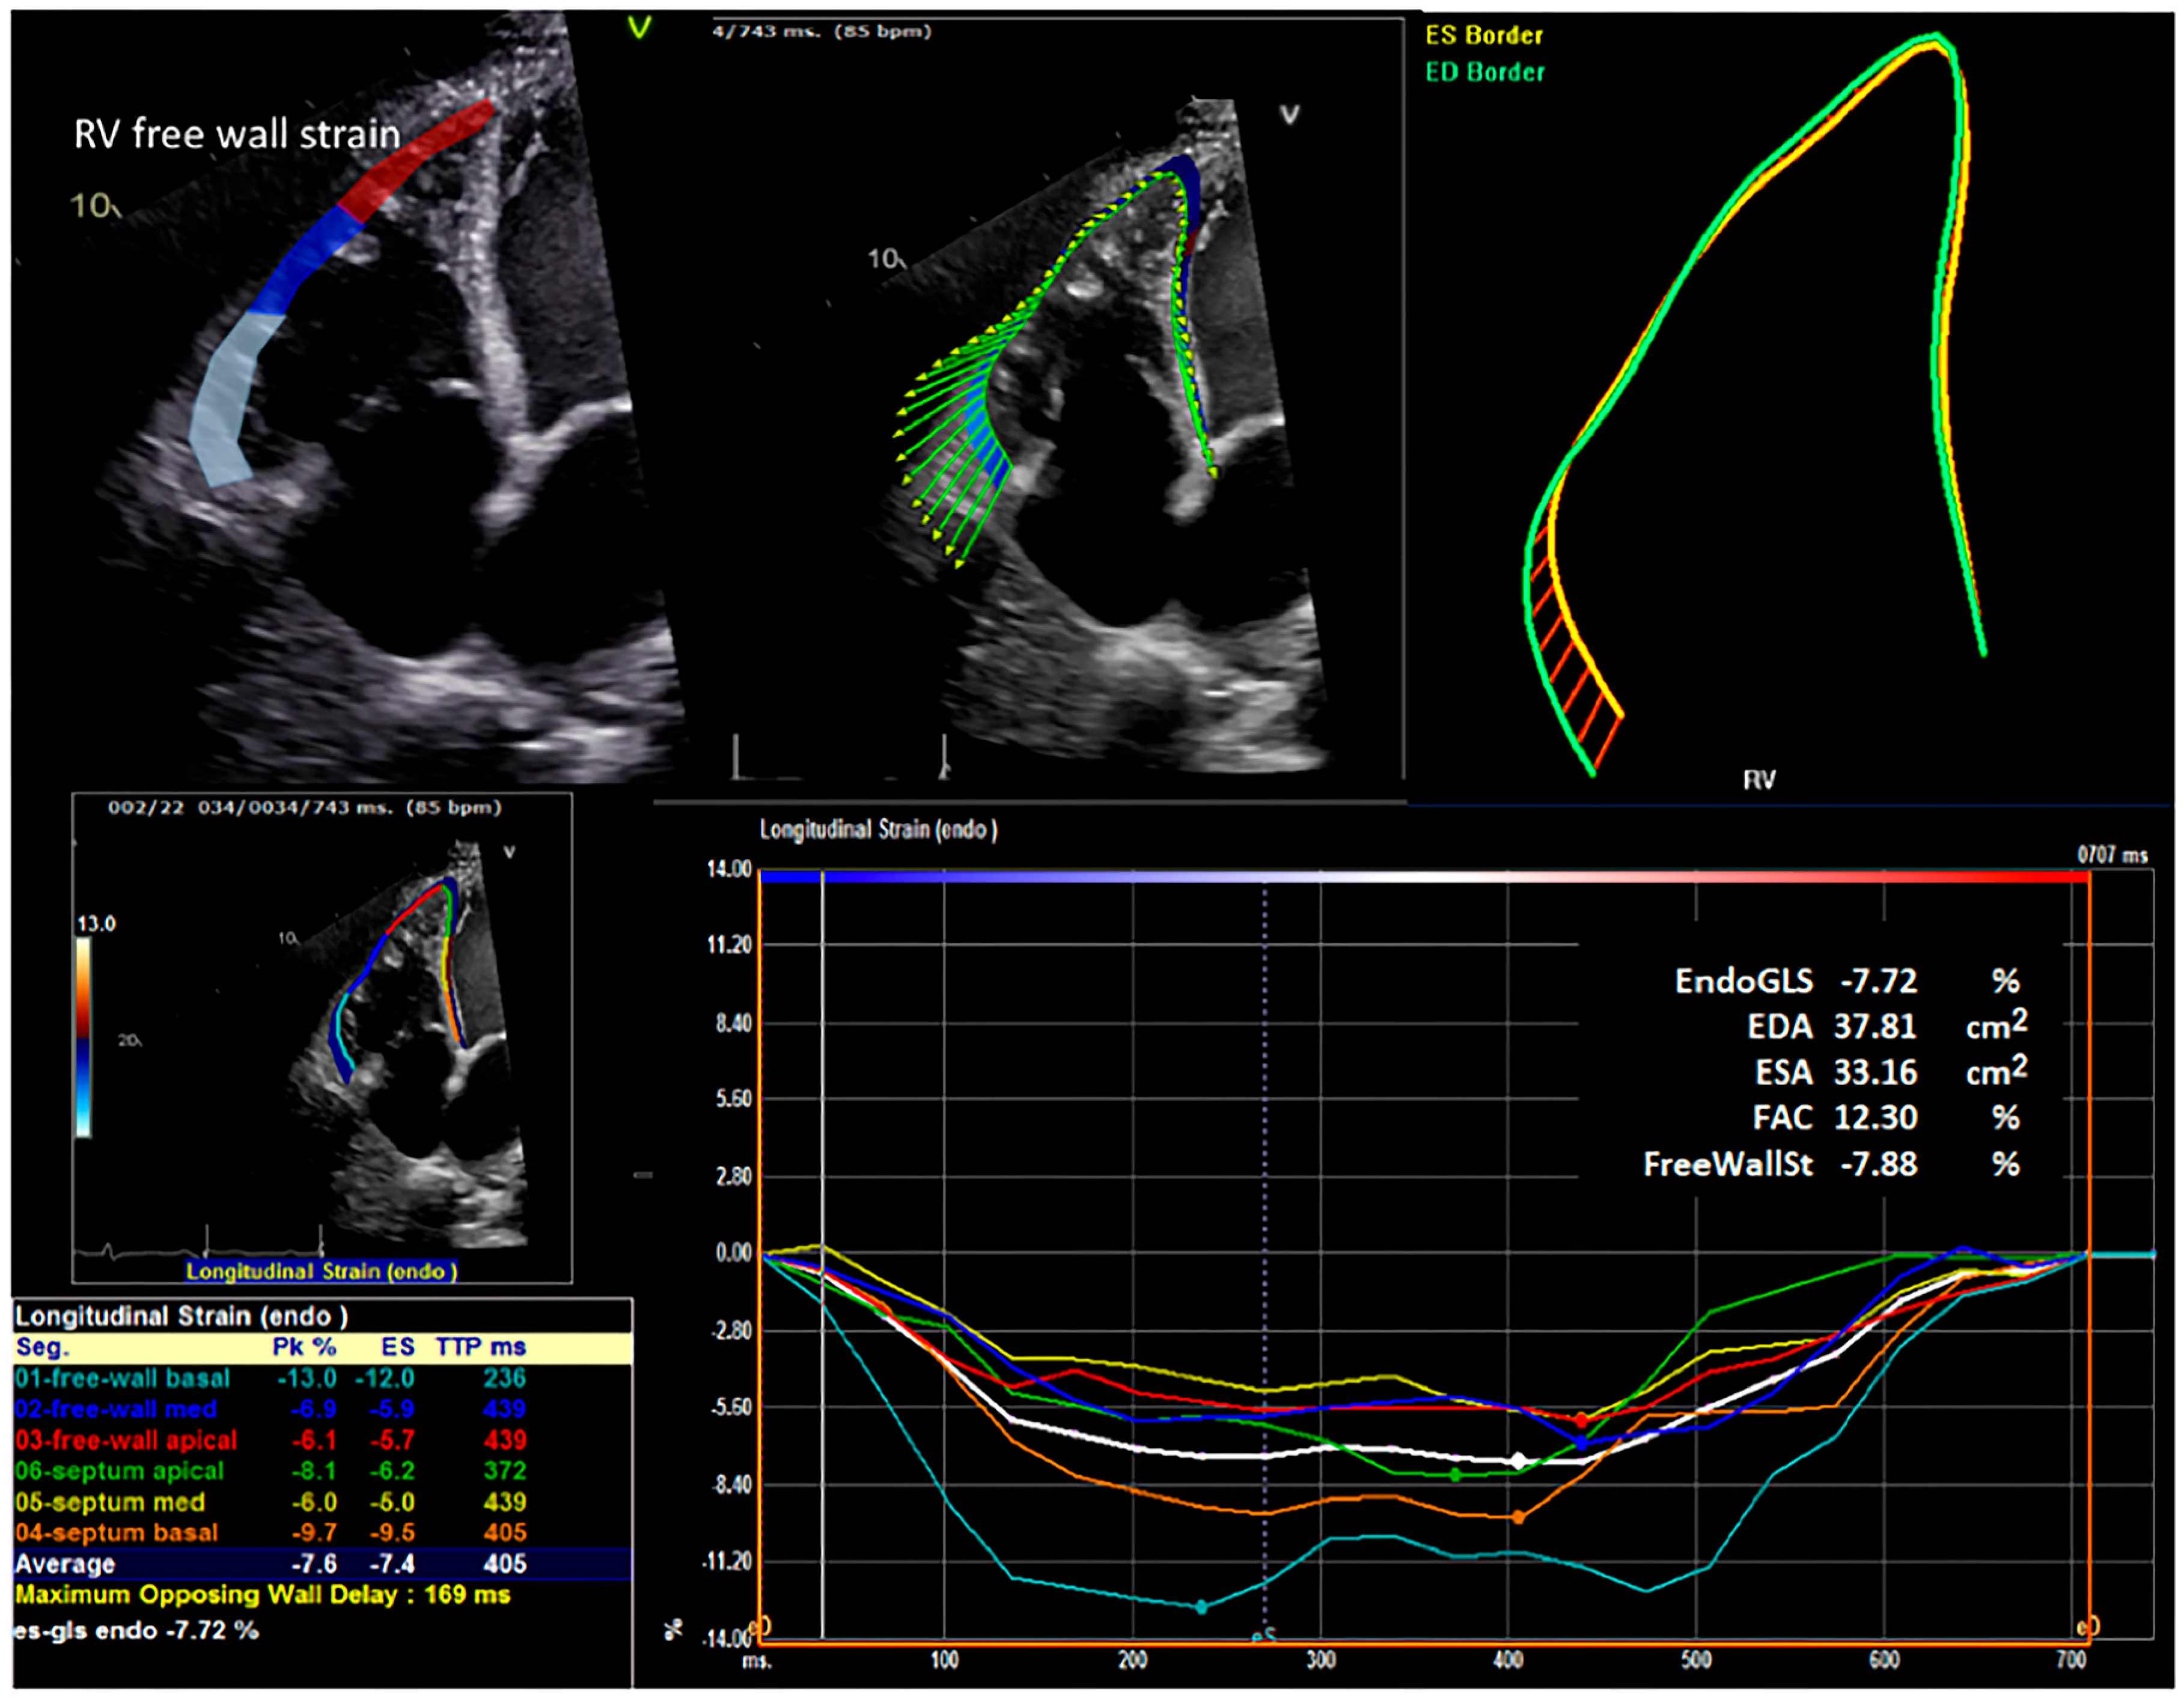

2.4. Strain Analysis

| Right ventricular free wall strain (%) | −5.1 | (−9.8, −3.9) | −6.7 | (−9.0, −4.5) | 0.40 |

| Right ventricular free wall strain (%) | −8.0 | (−10.2, −5.1) | −6.0 | (−8.6, −4.2) | 0.07 |